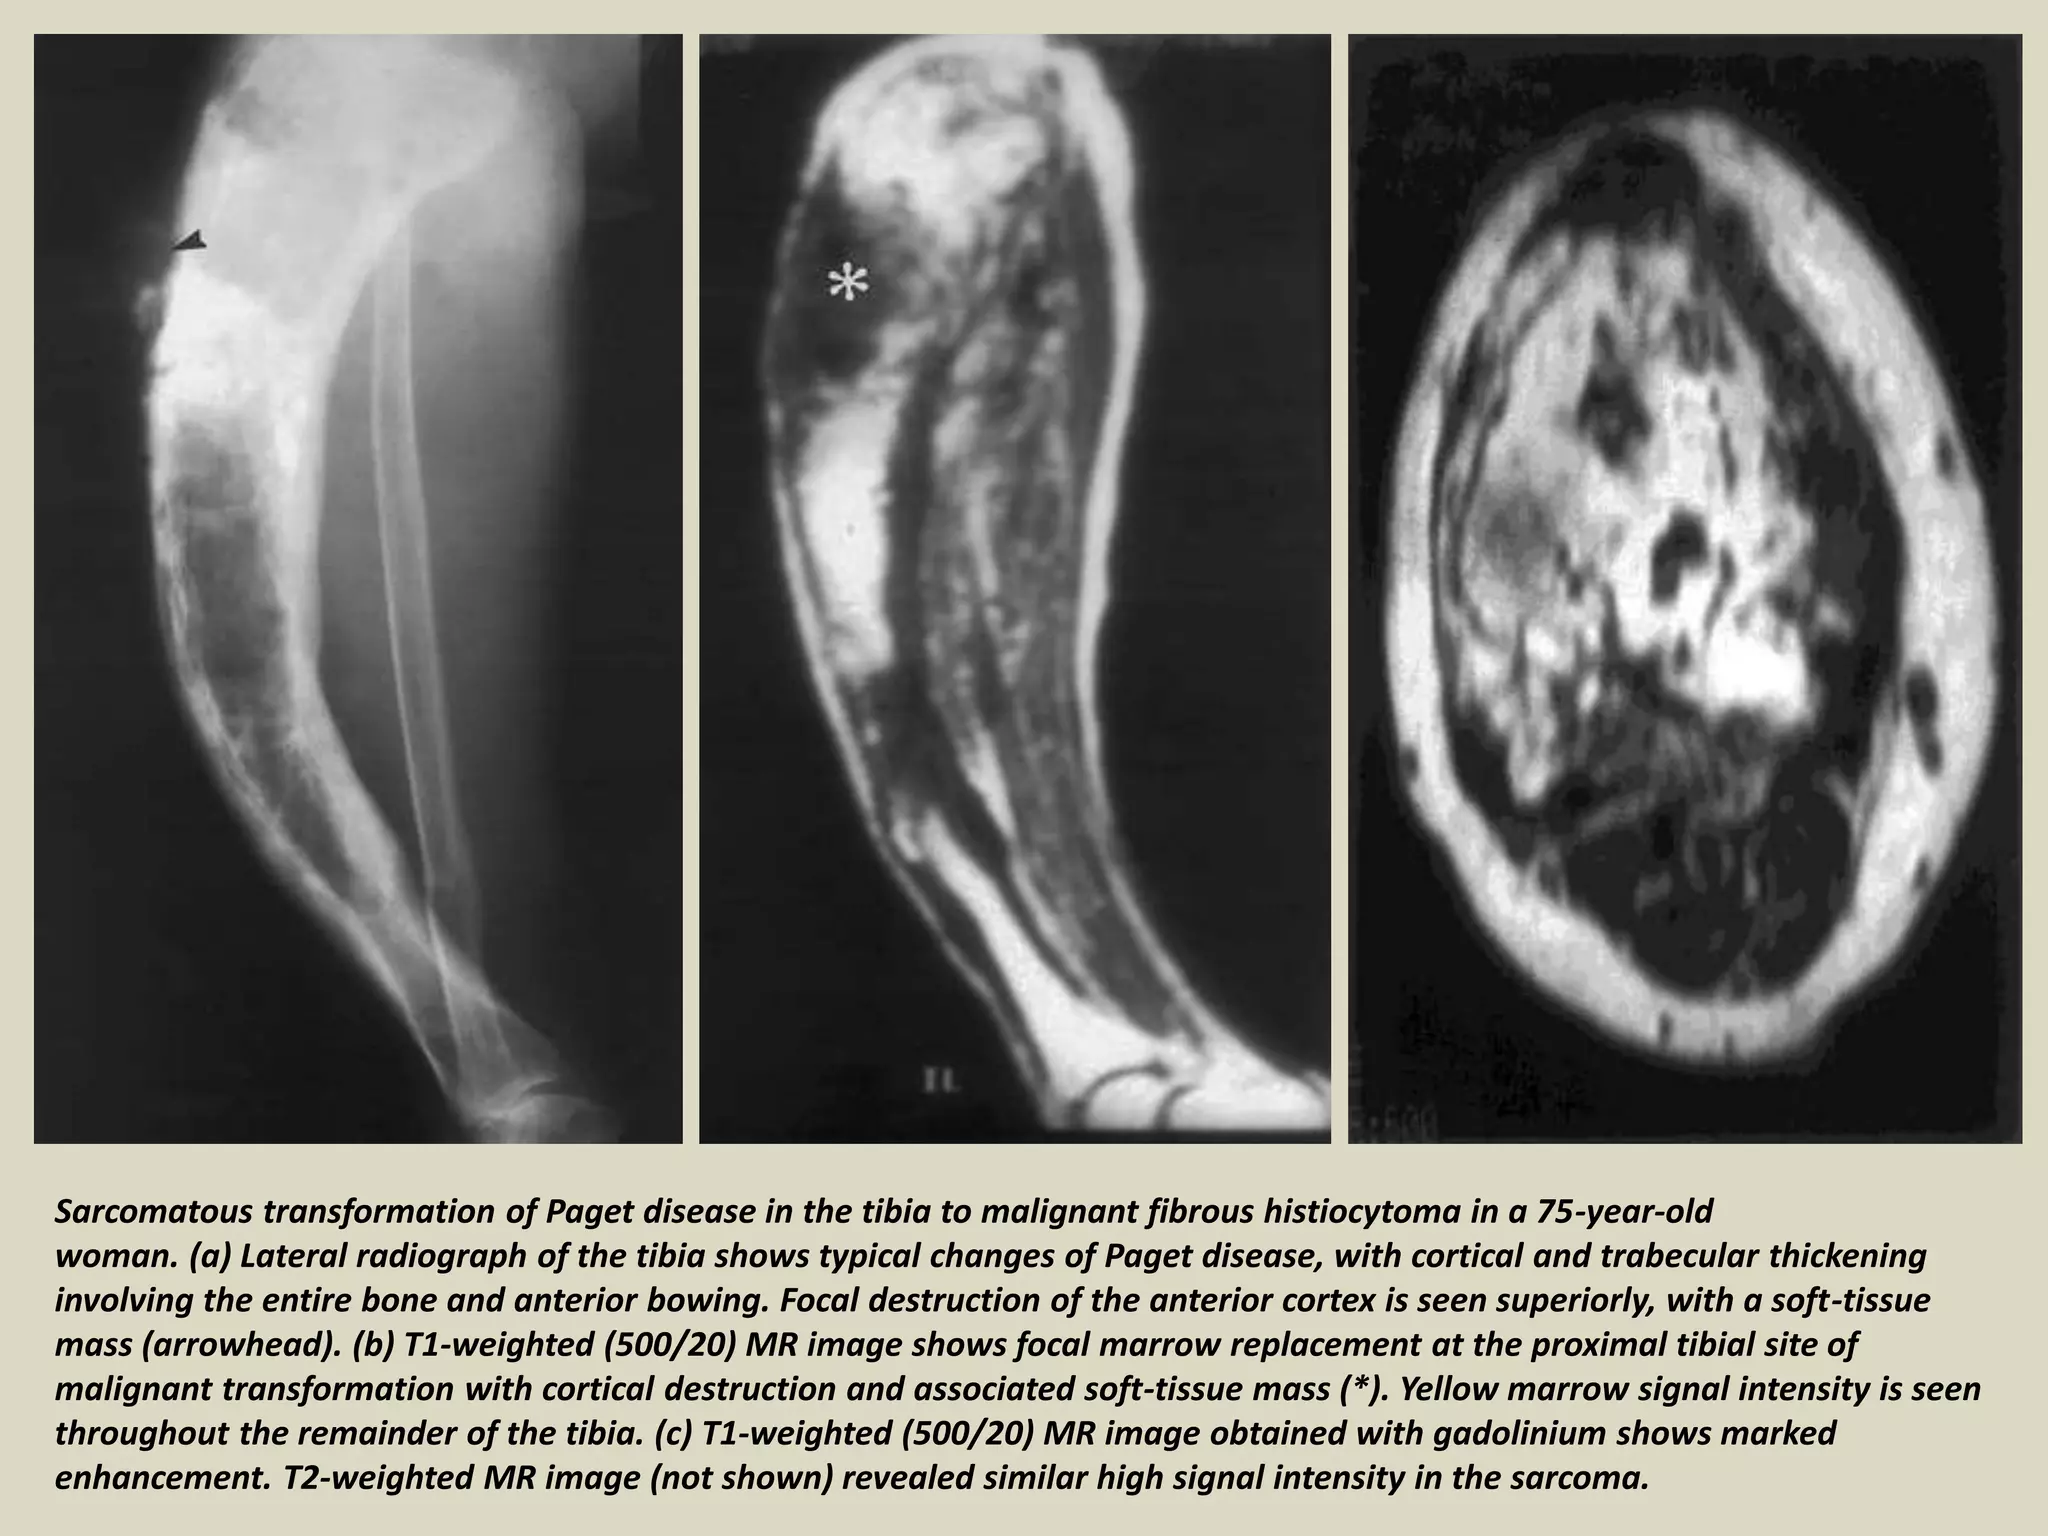

Sarcomatous transformation of Paget disease in the tibia to malignant fibrous histiocytoma in a 75-year-old

woman. (a) Lateral radiograph of the tibia shows typical changes of Paget disease, with cortical and trabecular thickening

involving the entire bone and anterior bowing. Focal destruction of the anterior cortex is seen superiorly, with a soft-tissue

mass (arrowhead). (b) T1-weighted (500/20) MR image shows focal marrow replacement at the proximal tibial site of

malignant transformation with cortical destruction and associated soft-tissue mass (*). Yellow marrow signal intensity is seen

throughout the remainder of the tibia. (c) T1-weighted (500/20) MR image obtained with gadolinium shows marked

enhancement. T2-weighted MR image (not shown) revealed similar high signal intensity in the sarcoma.